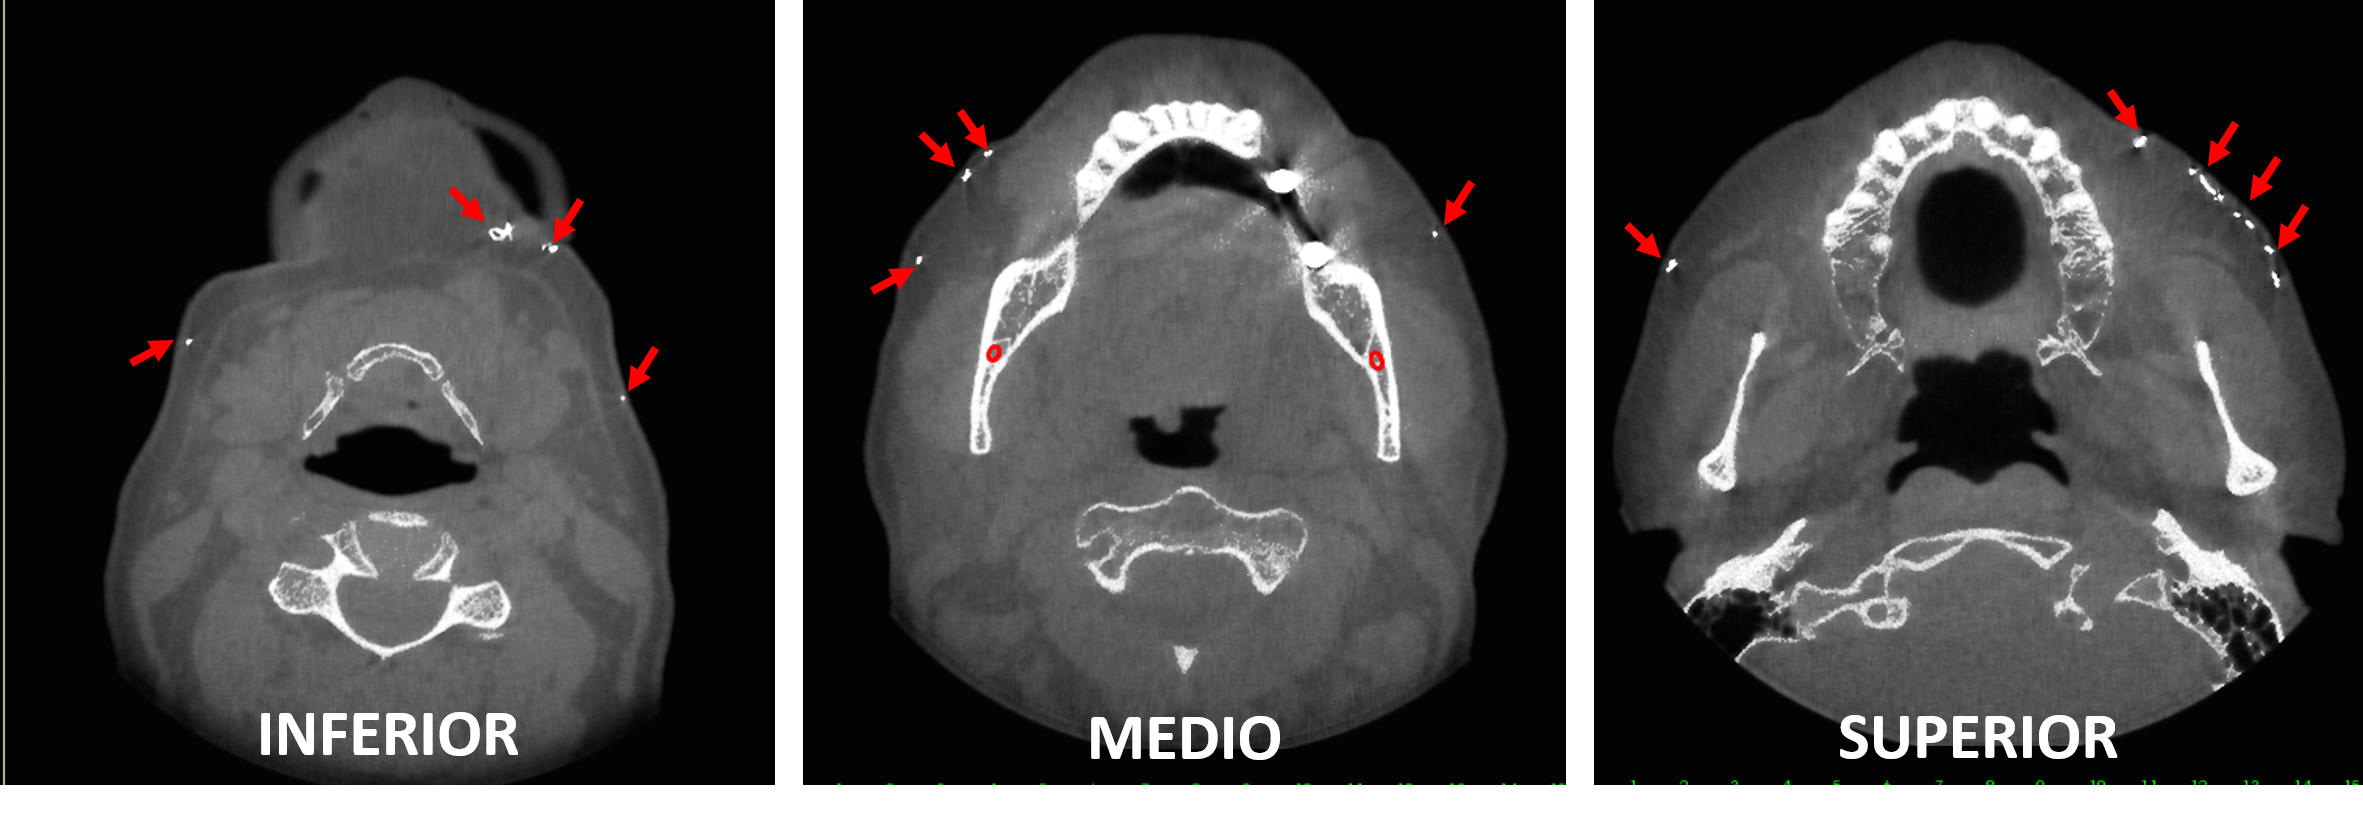

Fig.2

En cortes axiales (Fig.2) y en cortes coronales (Fig.3) se observan múltiples imágenes hiperdensas en la región submandibular, y en la región geniana en ambos lados del tejido blando facial (fechas rojas).